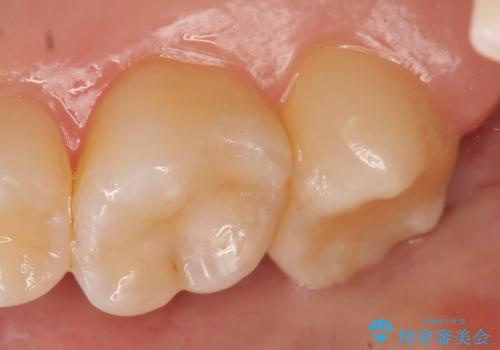

右上6番目、7番目の歯の樹脂が劣化していたため、虫歯除去後セラミックインレーによる修復を行いました。

当院のセラミックインレーはemaxという強度と審美性に優れた材料を使用しています。

またプレス方式でインレーを製作しているため、削り出しで製作するCADCAMより優れた適合性も持ち合わせており、虫歯が再発しにくい修復物です。